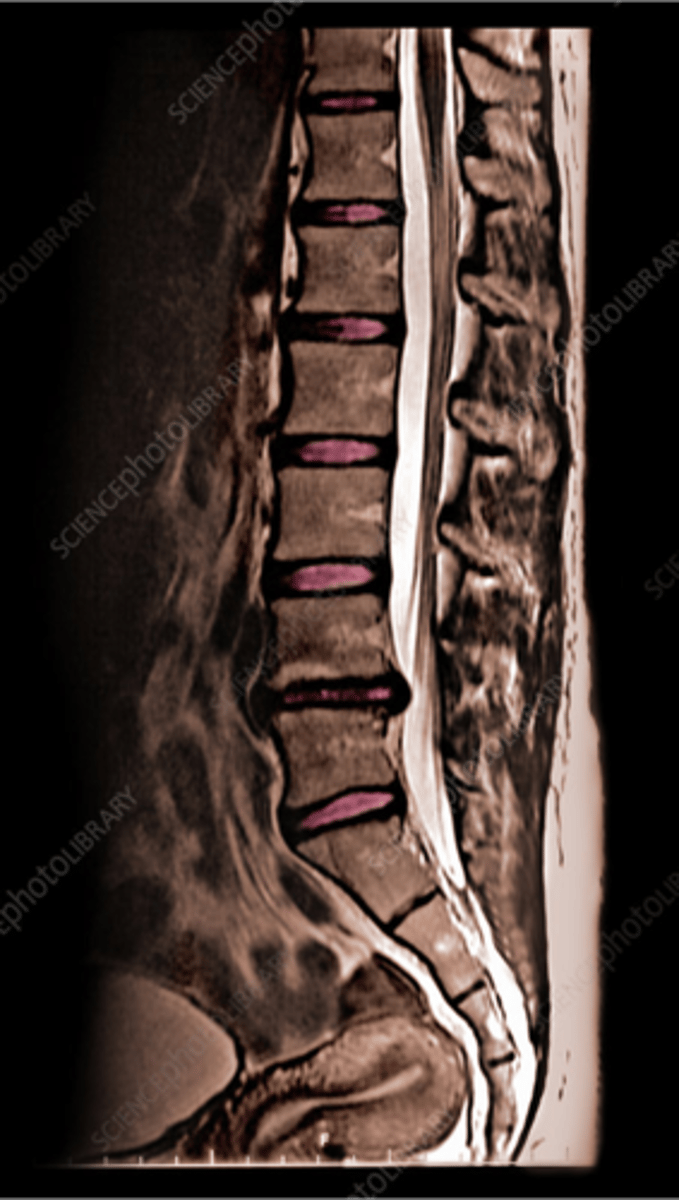

describe

normal MRI

what is wrong

there's a compression fracture on the third one down

vertebral compression fracture